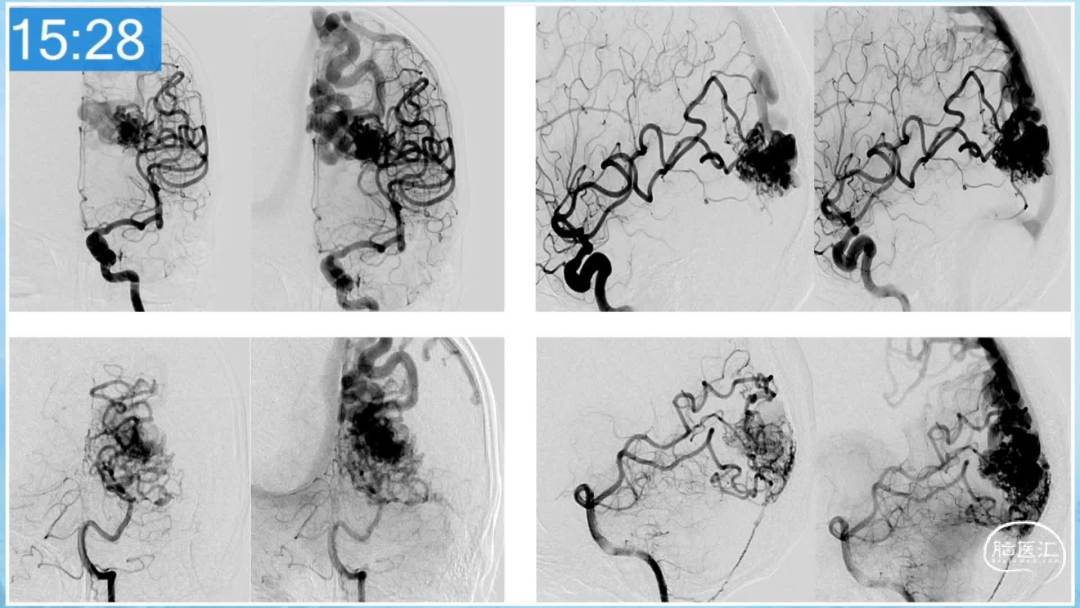

本期为大家特别分享:空军军医大学唐都医院邓剑平教授的精彩会议内容《颅内动静脉畸形的复合手术治疗》,欢迎大家阅读和分享!